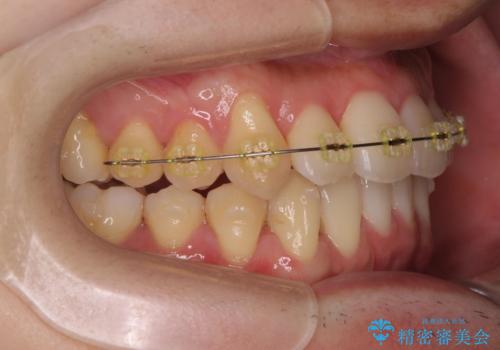

- インビザライン +部分ワイヤー矯正

4本の小臼歯抜歯を避け、下顎前歯の1本抜歯の極力少ない抜歯本数で審美的な歯並びを得る治療計画としました。

すれ違いを治すのが得意な前歯部の部分ワイヤーを用いることで、治療期間を短縮することができました。